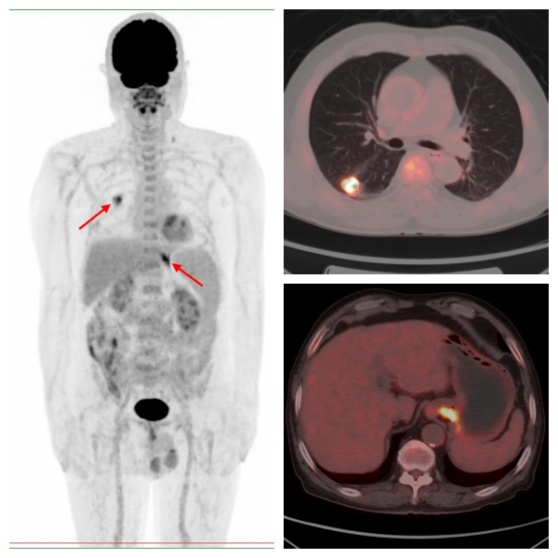

病例1,PET/CT示右肺下葉、賁門代謝異常,符合雙原發(fā)癌;之后患者行CT引導下肺部病變穿刺,病理證實原發(fā)肺腺癌,行胃鏡下賁門病變活檢,病理證實原發(fā)賁門腺癌。